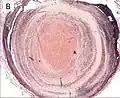

A recent pulmonary thrombo-embolus with prominent lines of Zahn. The pale areas consist of fibrin and platelets. The red areas consist of erythrocytes.

Lines of Zahn are a characteristic of thrombi. They have layers, with lighter layers of platelets and fibrin, and darker layers of red blood cells. They are more present on thrombi formed with faster blood flow, more so on thrombi from the heart and aorta. They are only seen on thrombi formed before death. They are named after German–Swiss pathologist Friedrich Wilhelm Zahn.

Lines of Zahn are a characteristic of thrombi.[1] They have visible and microscopic alternating layers (laminations).[2][3] Platelets mixed with fibrin form lighter layers.[2] Red blood cells form darker layers.[2] Sometimes, the term "lines of Zahn" only refers to the lighter layers.[4]